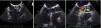

At 18-month follow-up she presented worsening functional capacity with dyspnea on moderate exertion (New York Heart Association class II). TTE was repeated and showed marked LV hypertrophy of the basal IVS and good global systolic function; an apparently tricuspid AV, calcified, with reduced opening, that could not be assessed by planimetry; and a calcified mitral valve with systolic anterior motion (SAM). Doppler study revealed accelerated flow beginning in the LVOT, with peak velocity at mid-systole and peak and mean LV/Ao gradient of 49 mmHg and 32 mmHg, respectively, supporting the hypothesis of a fixed obstruction (Figure 3). No late-systolic velocity peak was observed, with or without the Valsalva maneuver.

Transthoracic echocardiography: (left) color Doppler showing turbulent flow beginning in the left ventricular outflow tract; (right) continuous-wave Doppler showing rounded waveform with mid-systolic peak (bell-shaped) and peak and mean left ventricular/aortic gradient of 49 mmHg and 32 mmHg, respectively.